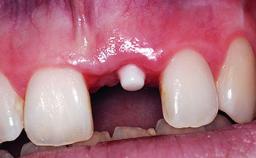

A 36-year-old male patient with a compromised maxillary central incisor was referred by his general dentist for consultation. The patient’s chief complaints were the gradual debonding of a temporary crown on the right central incisor and unsatisfactory esthetics due to an increasing diastema between the right central and lateral incisors. The patient reported a traumatic event some years previously, when a crown had been placed after root-canal treatment. The referring dentist wanted to provide a new crown restoration, but was concerned about the condition of the residual root. Anamnesis was negative for any other dental or periodontal pathology in the remaining dentition. The patient reported taking no medications: He was a smoker (10 to 15 cigs/day) and had realistic esthetic expectations.